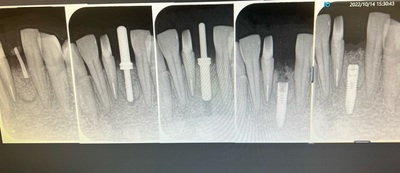

術前

IMG_6004.jpg

当然、隣の歯牙も根管治療からやり直し。

抜歯2ヶ月後の待機埋入。